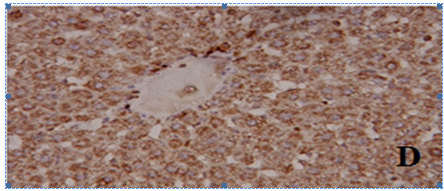

Fig. 5: Photomicrographs of liver tissue. Where A) represents control, B) aluminum chloride (AlCl3), C) zinc oxide nanoparticles (ZnO NPs) and D) aluminum chlorid (AlCl3)+zinc oxide nanoparticles (ZnO NPs)

Effect of ZnO NPs and/or AlCl3 treatment on liver histopathology

As shown in fig. 5, the control group exhibited normal hepatocytes architecture showing well-defined central nucleus and abundant cytoplasm, while the hepatic tissue of the AlCl3-intoxicated animals indicated as previously recorded [5] by alterations in hepatic histo-architecture after 6 w of treatment evidenced by disrupted central vein and disarrangement of hepatic cords at most of the places and, also, vacuolated hepatocytes, leukocytes infiltration and many Kupffer cells and hepatocytes with dense and pyknotic nuclei were observed. ZnO NPs administration to animals for 6 w also showed vacuolization and disrupted hepatic cords.

While ZnO NPs+AlCl3 treated group indicated revealed that pre-administration of ZnO NPs preserved, to some extent, the hepatic tissue from these pathological alterations caused by AlCl3 exposure.